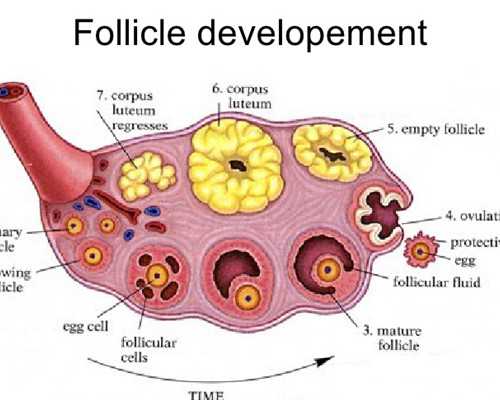

當(dāng)女方來(lái)例假第二天開(kāi)始進(jìn)入試管嬰兒周期,第一步就是促排,通過(guò)藥物給予卵泡一定的營(yíng)養(yǎng),使多個(gè)卵泡能夠同時(shí)發(fā)育成熟,提高受孕率,因?yàn)槊總€(gè)人的卵巢反應(yīng)程度不同,方案和用藥量也不同,所以費(fèi)用會(huì)有一定差異。